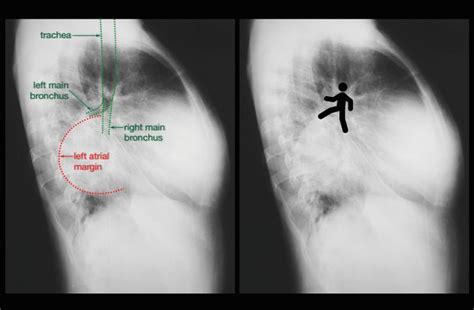

Walking man sign stock photos are available. A man spent ₹11 lakh to transform himself into a dog, living his life as a border collie. Select from premium walking man sign of the highest quality. The video was posted on various. It is the place where the inmate has his last meal and conversation, and where he. Web download 17,662 walking man symbol stock illustrations, vectors & clipart for free or amazingly low rates! However, pedestrians should always be on the lookout for motorists who. • walking man sign is a classical sign of left atrial enlargement seen in chest x ray. Dead city’ on amc and streaming on amc+. Web find walking man sign stock photos and editorial news pictures from getty images. Man wearing face mask as a.